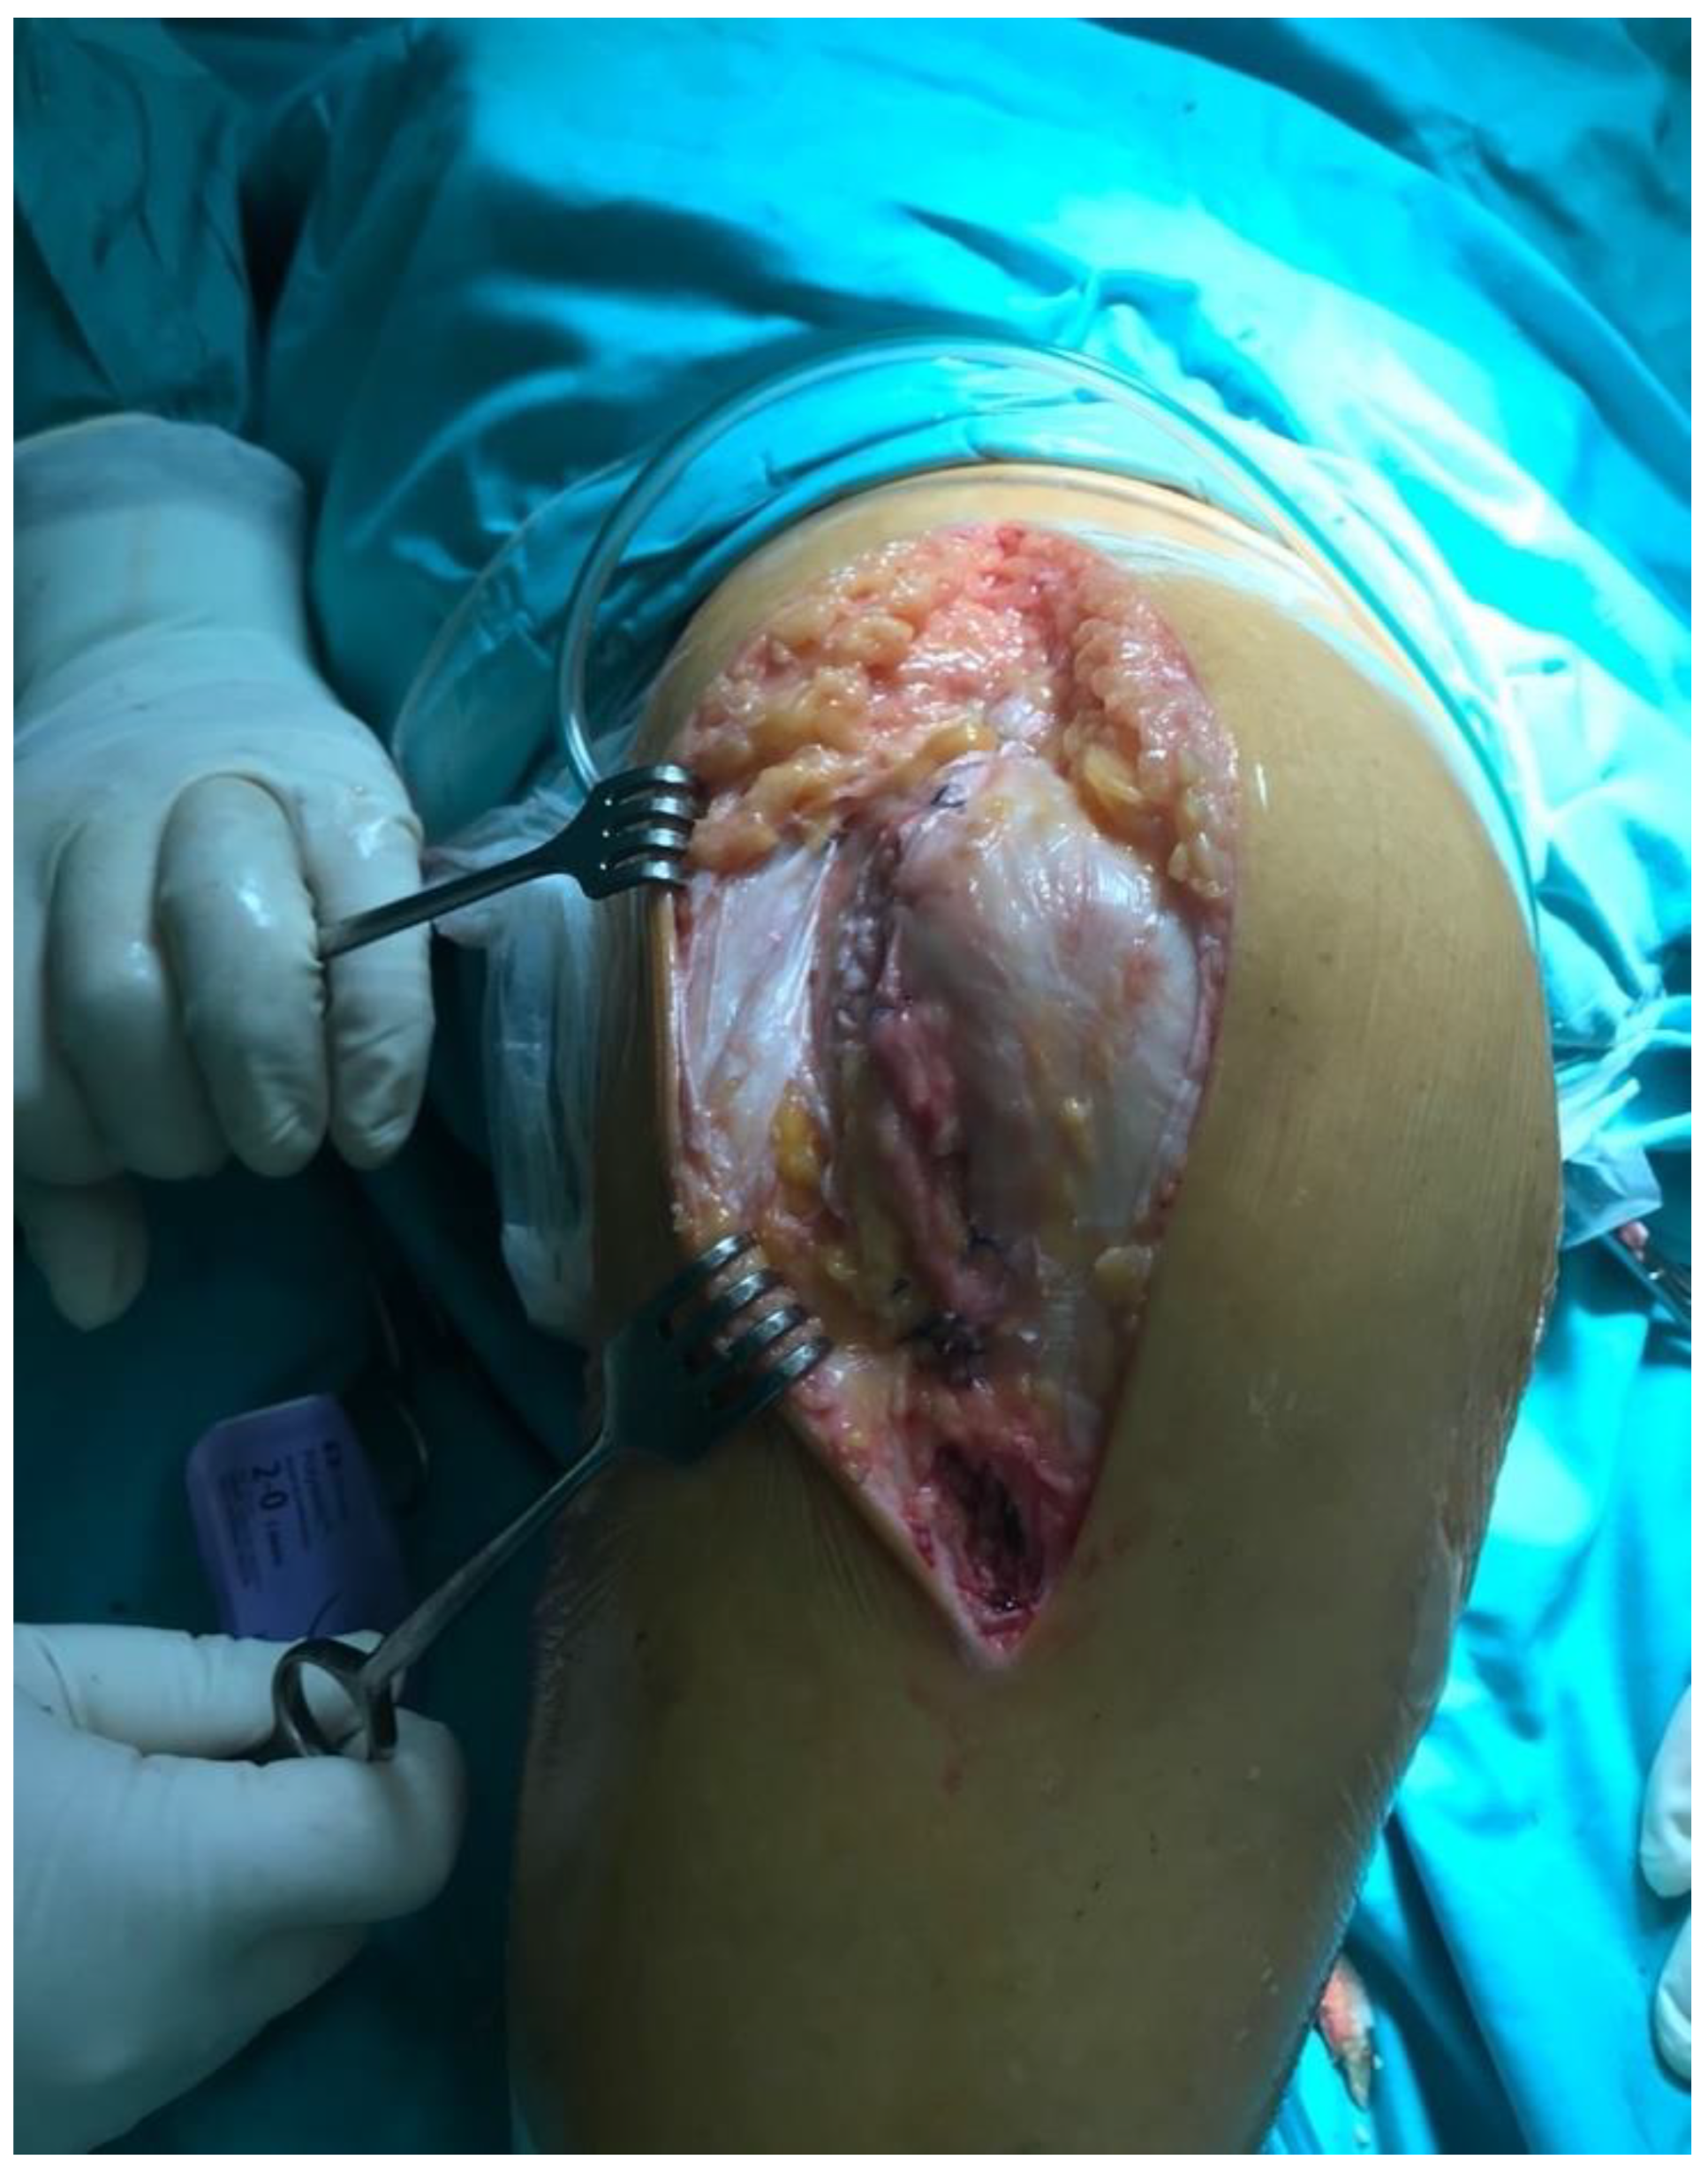

2.2. Surgical Approach